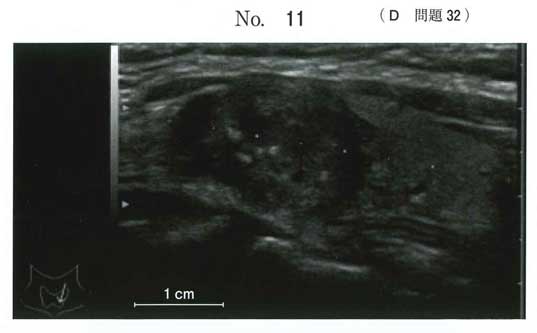

dです。

微細石灰化を伴う甲状腺乳頭癌